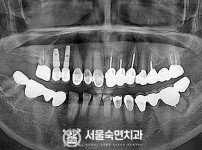

임플란트-전후사진4